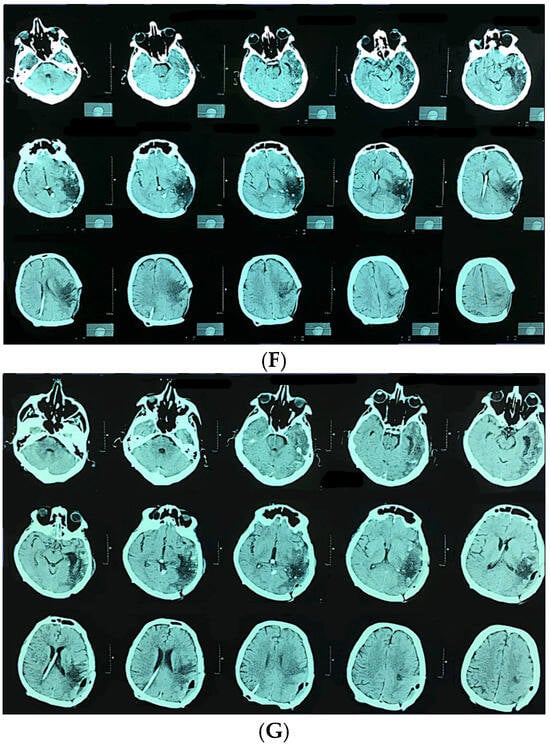

All patients underwent standardized postoperative clinical follow-up with assessment of the modified Rankin Scale (mRS). Postoperative outcomes were evaluated based on the occurrence of rebleeding or new hemorrhage on imaging, and the presence of new, persistent neurological deficits. Radiological confirmation of complete obliteration was recorded for majority of patients, though it is acknowledged that angiographic data were not obtained for the entire cohort (Figure 1).

Figure 1.

Kaplan-Meier survival curve.

Kaplan–Meier survival analysis was performed to compare overall survival between patients with and without hemorrhage. As shown in the survival curves, both groups demonstrated high cumulative survival throughout the observation period. The non-hemorrhage group exhibited an initial survival probability of 1.0, with a single decline to approximately 0.87 following one recorded event. Similarly, the hemorrhage group showed a survival drop to approximately 0.90 after its first event. Censored observations in both groups are indicated by “+” markers at the end of individual follow-up times.

The survival trajectories of the two groups were largely overlapping, with no substantial divergence across the follow-up interval. This visual similarity suggests that the presence of hemorrhage did not meaningfully affect overall survival within the study period (Figure 2 and Figure 3).